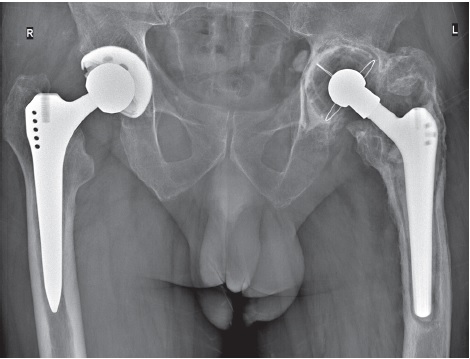

Описание случая. Представлен сложный клинический случай лечения пациента 62 лет с дефицитом костной ткани в области вертлужной впадины IIА типа по Paprosky и проксимального отдела бедренного кости типа II по Paprosky с асептическим расшатыванием ацетабулярного и бедренного компонентов эндопротеза. В ходе ревизионного эндопротезирования с использованием компонентов эндопротеза цементной фиксации выполнена импакционная костная пластика вертлужной впадины и бедренной кости с аугментацией реконструктивной сеткой надацетабулярного массива по технологии Stryker X-Change. В качестве костнопластического материала использована аллокость, заготовленная с помощью метода термодезинфекции. Срок наблюдения составил 4 года. Контрольные рентгенограммы демонстрируют восстановление центра ротации тазобедренного сустава и костного массива в области дефектов тазовой и бедренной костей, отсутствие резорбции костнопластического материала и миграции эндопротеза. При кинической оценке состояния по шкале Harris отмечено улучшение с 34 до 85 баллов.

На предоперационной рентгенограмме (рис. 1) от 30.07.2018 г. определялось:

Рис. 1. Обзорная рентгенограмма таза до ревизионного вмешательства на левом тазобедренном суставе (объяснение в тексте)

Fig. 1. Plain pelvis X-ray before revision of the left hip (explanation in the text)

На контрольной рентгенограмме от 03.08.2018 г. после выполненного ревизионного эндопротезирования и реконструкции вертлужной впадины с применением сетки и ИКП, реконструкции проксимального отдела бедренной кости с помощью ИКП и использованием цементной ножки Stryker Exeter костнопластический материал равномерно заполняет вертлужную впадину. Задний край впадины аугментирован реконструктивной сеткой, расположение бедренного компонента правильное, параллельно оси бедренной кости; заполнение бедренного канала костнопластическим материалом равномерное, одинаковой интенсивности во всех зонах. Рентгенопрозрачных линий на границе «костнопластический материал — цемент» не наблюдается (рис. 3 a).

Рис. 3. Обзорные рентгенограммы таза после ревизионного вмешательства на левом тазобедренном суставе: a — контрольная рентгенограмма сразу после операции (02.08.2018): отмечается равномерное распределение костнопластического материала, восстановление центра ротации сустава; b — через 4 мес. (24.12.2018): положение компонентов прежнее, миграции тазового и бедренного компонентов не наблюдается, состояние костнопластического материала удовлетворительное, без признаков резорбции, отсутствие рентгенопрозрачных линий на границе «костнопластический материал — цемент»; с — через 4 года (24.10.2022): рентгенологические признаки перестройки костнопластического материала в тазовой и бедренной костях, отсутствуют линии просветления на границе «костнопластический материал — цемент», положение компонентов эндопротеза прежнее — без признаков миграции или проседания

Fig. 3. Plain pelvis X-rays after the left hip revision: a — control X-ray immediately after the surgery (02/08/2018): even distribution of osteoplastic material, restoration of the center of rotation of the joint; b — 4 months after the surgery (24/12/2018): position of components remains unchanged, no migration of the acetabular and femoral components is observed, the state of osteoplastic material is satisfactory with no signs of resorption; radiolucent lines at the osteoplastic material-cement interface are absent; c — 4 years after the surgery (24/10/2022): X-ray signs of restructuring of osteoplastic material in the pelvic and femoral bones, radiolucent lines at the osteoplastic material-cement interface are absent, position of components remains unchanged with no signs of migration or subsidence